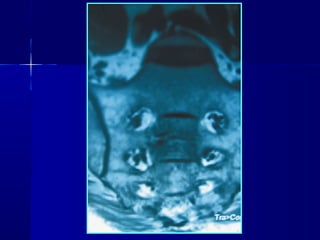

CT SCAN

• TThhee mmoosstt aaccccuurraattee

• EEssppeecciiaallllyy ffoorr ttrraannssvveerrssee ffrraaccttuurreess

• UUsseeffuull ffoorr ddeetteeccttiinngg llaarrggee ddeeffeeccttss aass ttaarrlloovv ccyyssttss

• DDiiaaggnnoossiiss ooff ccooeexxiissttiinngg mmaalliiggnnaanntt lleessiioonnss